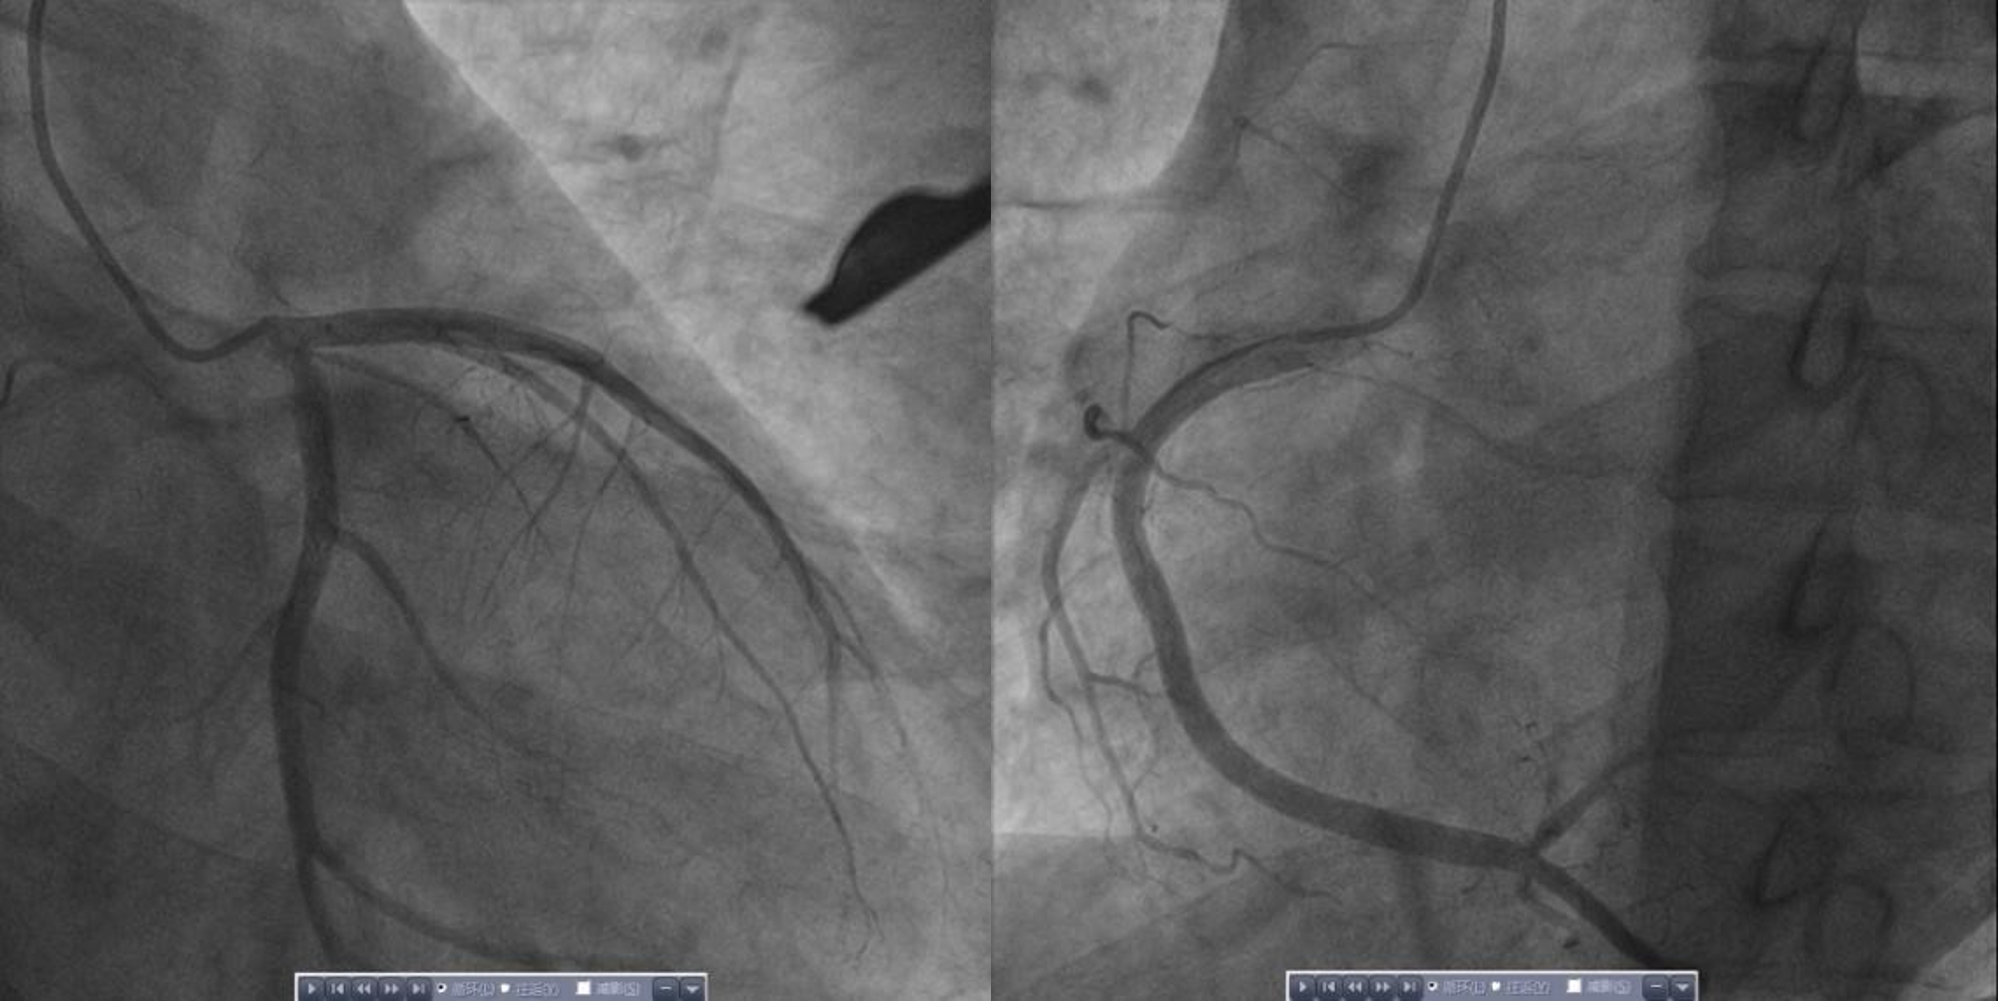

今年49岁的张先生,几日前自觉“上火”,虽有眼干、流涕,伴乏力等症状,但起初并未在意,几日来症状并无好转,且出现了进行性加重的胸闷气促。8月1日,患者自觉“熬不住了”,遂在家属陪同下前往苏州大学附属独墅湖医院急诊就诊。医生接诊后,发现患者面色苍白,气促明显,精神萎靡,呈休克状态,且心电图提示胸前导联广泛ST段弓背向上抬高、三度房室传导阻滞等。心内科医生急会诊后,结合查体及检验,初步判断为急性心肌梗死/心肌炎,并迅速启动急诊冠脉造影。术中患者胸闷气促明显,提示存在严重左心衰。然而造影显示冠脉无明显狭窄,结合患者病史及检查,初步诊断为急性重症心肌炎、心源性休克、三度房室传导阻滞、急性心力衰竭、低氧血症、肝功能不全、肾功能不全。

图1 入院急诊冠脉造影结果